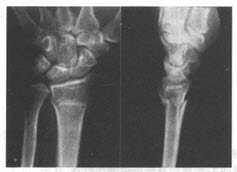

患者,男,31岁。不慎摔倒后手掌撑地,右腕部疼痛1小时,拍摄腕关节正侧片如图。

下列描述正确的是()

A:Smith骨折的骨折两端向掌侧成角

B:Colles骨折的骨折两端向背侧成角

C:Colles骨折的骨折远端向桡侧移位

D:Colles骨折的骨折远端向背侧移位

E:Smith骨折又称反Colles骨折

F:Colles骨折典型者伤手呈银叉畸形